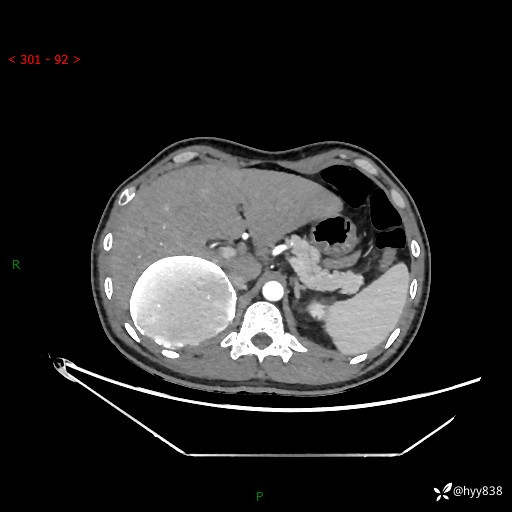

性别:男

年龄:50岁

简要病史:夜尿增多半月,发现肾功能异常1天,超声发现腹膜后占位

腹部CT平扫+增强

增强